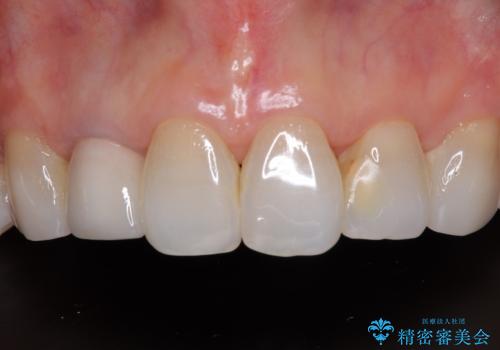

長年口を開ける度に気になっていた銀歯が一気に自然な色合いとなり、患者様には大変満足していただけました。